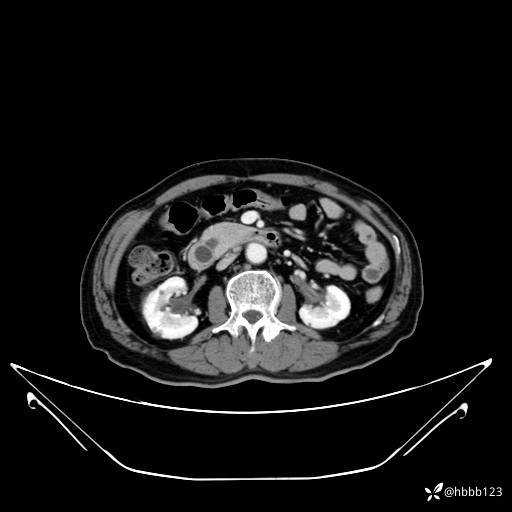

平扫: